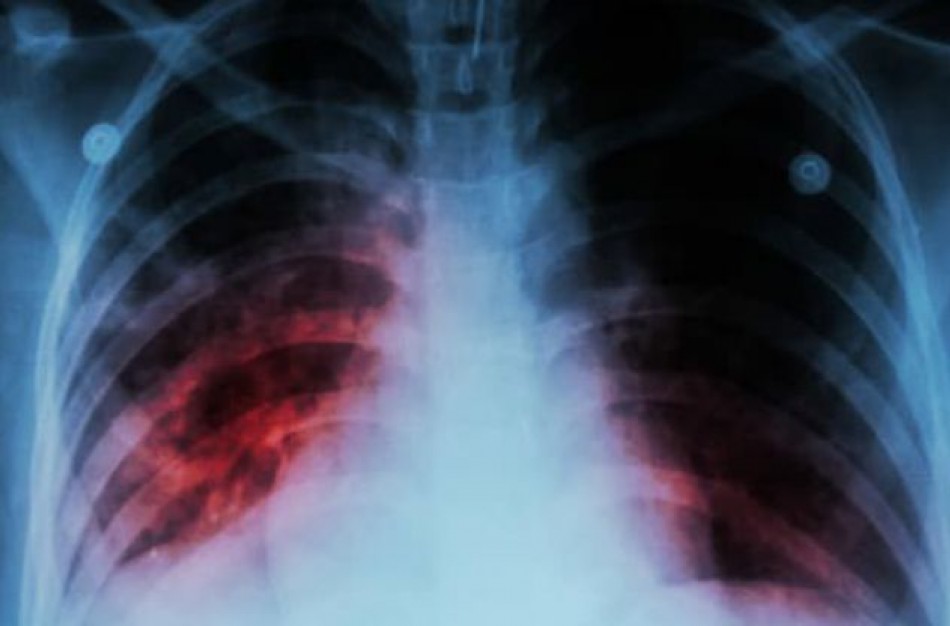

NVSC Kauno departamento specialistai primena, kad pagrindinis tuberkuliozės užsikrėtimo šaltinis yra žmogus, kuris serga atvira plaučių tuberkuliozės forma. Tuberkuliozės bakterijos patenka į orą, kai plaučių tuberkulioze sergantis žmogus kalba, kosėja ar čiaudi. Bakterijos ore gali išlikti kelias valandas, priklausomai nuo aplinkos sąlygų. Žmogus, įkvėpęs bakterijomis užteršto oro, gali užsikrėsti. Užsikrėtę asmenys savo organizme turi tuberkuliozės bakterijų, bet daugumai jos nėra aktyvios ir nesukelia ligos, nepasireiškia tuberkuliozei būdingi požymiai ir žmogus neplatina ligos sukėlėjo. Nustatyta, kad tik dalis užsikrėtusių asmenų (5-10 proc.) gali susirgti arba suserga tuberkulioze.

Tuberkuliozės simptomai pasireiškia, kai tuberkuliozės bakterijos žmogaus organizme tampa aktyvios, t. y. pradeda daugintis.

Pagrindiniai tuberkuliozės simptomai, kuriuos pajutus reikėtų kreiptis į savo šeimos gydytoją:

⦁ kosulys, trunkantis 3 ar daugiau savaičių;

⦁ kosėjimas su skrepliais ar su krauju.